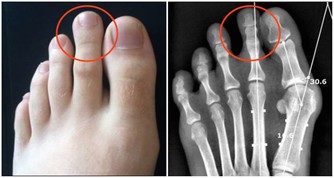

根據耳穴的分佈圖,可以發現我們常規穿耳洞的位置,正面和背面分別對應的是眼和腎,通過耳環的自重以及活動中產生的摩擦作用,不斷刺激此處的穴位,達到聰耳明目的效果。

近視眼患者不妨多戴, 或可取得意想不到的效果,但耳環的選用不可過重,以防拉傷。